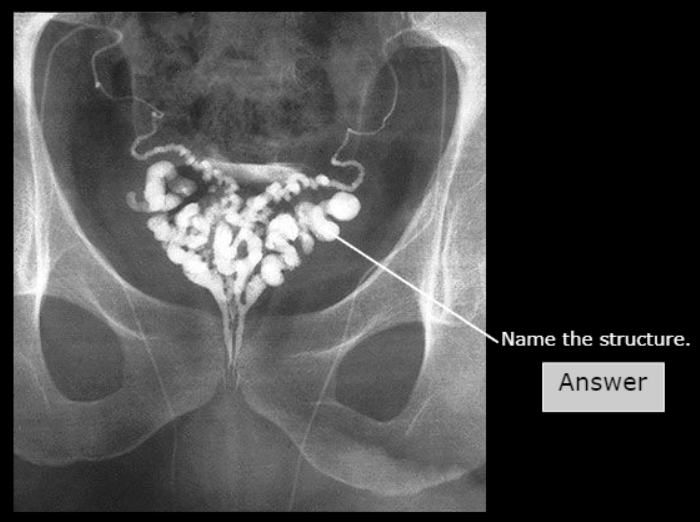

Fimbria of Uterine (fallopian) tube